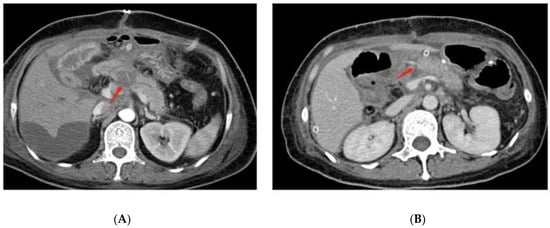

- Lee, H.-J.; Kim, J.W.; Hur, Y.H.; Lee, B.K.; Cho, S.B.; Hwang, E.C.; Lee, S.J.; Yoon, E.J.; Seon, H.J. Multidetector CT findings differ between surgical grades of pancreatic fistula after pancreaticoduodenectomy. Eur. Radiol. 2019, 29, 2399–2407. [Google Scholar] [CrossRef]

- Yang, J.; Li, Y.-C.; Liu, X.-B.; Tan, C.-L. Infection and image findings to predict delayed hemorrhage in postoperative pancreatic fistula patients after pancreaticoduodenectomy. Asian J. Surg. 2022, 45, 1130–1131. [Google Scholar] [CrossRef]